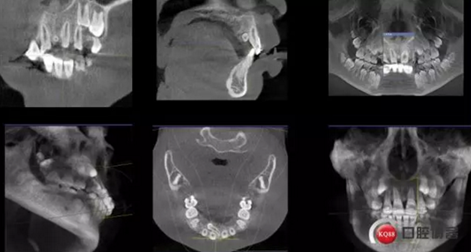

CBCT術(shù)前分析,精準找到牙齒的具體位置